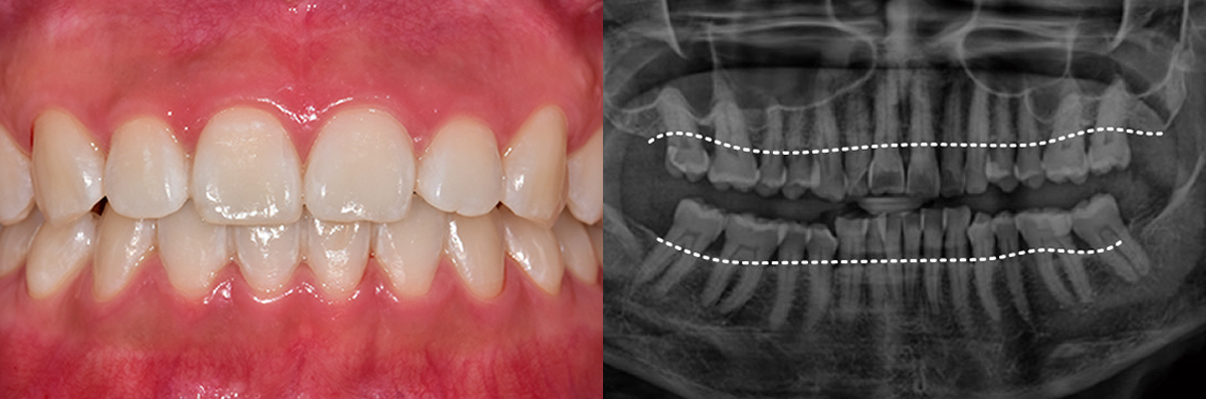

치주질환 그대로 방치한다면

잇몸뼈까지 소실됩니다

치주질환을 방치하면 뼈가 녹아내리며, 결국 발치에 이르게 됩니다.

잇몸이 무너진 후 치료는 더욱 어렵습니다.

잇몸이 붉지 않고, 연분홍빛을 띠며 단단하게 치아를 감싸고 있습니다. 엑스레이에서는 치아 뿌리를 따라 잇몸뼈가 치아 경계선 바로 아래까지 촘촘하게 유지되고 있습니다.